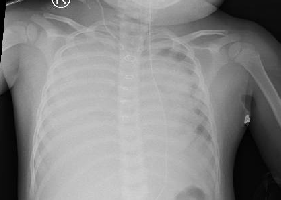

Vừa qua khoa Cấp cứu Bệnh viện Nhi Đồng Thành Phố, tiếp nhận một trường hợp trẻ CB. L. T. N. B.1,5 tháng tuổi, nam, ngụ tại Sóc Trăng, được chuyển đến trong...